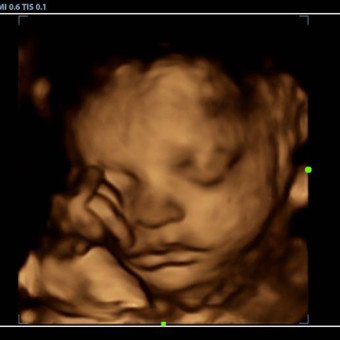

Hello everyone! We’re so excited to welcome baby girl K into the family. We ask if you purchase anything from the registry, make sure to go back and mark as purchased, especially if you buy from another website (like target or Amazon). This will help to avoid any duplicates, as it doesn’t do it automatically. Thank you for celebrating her with us 🥰